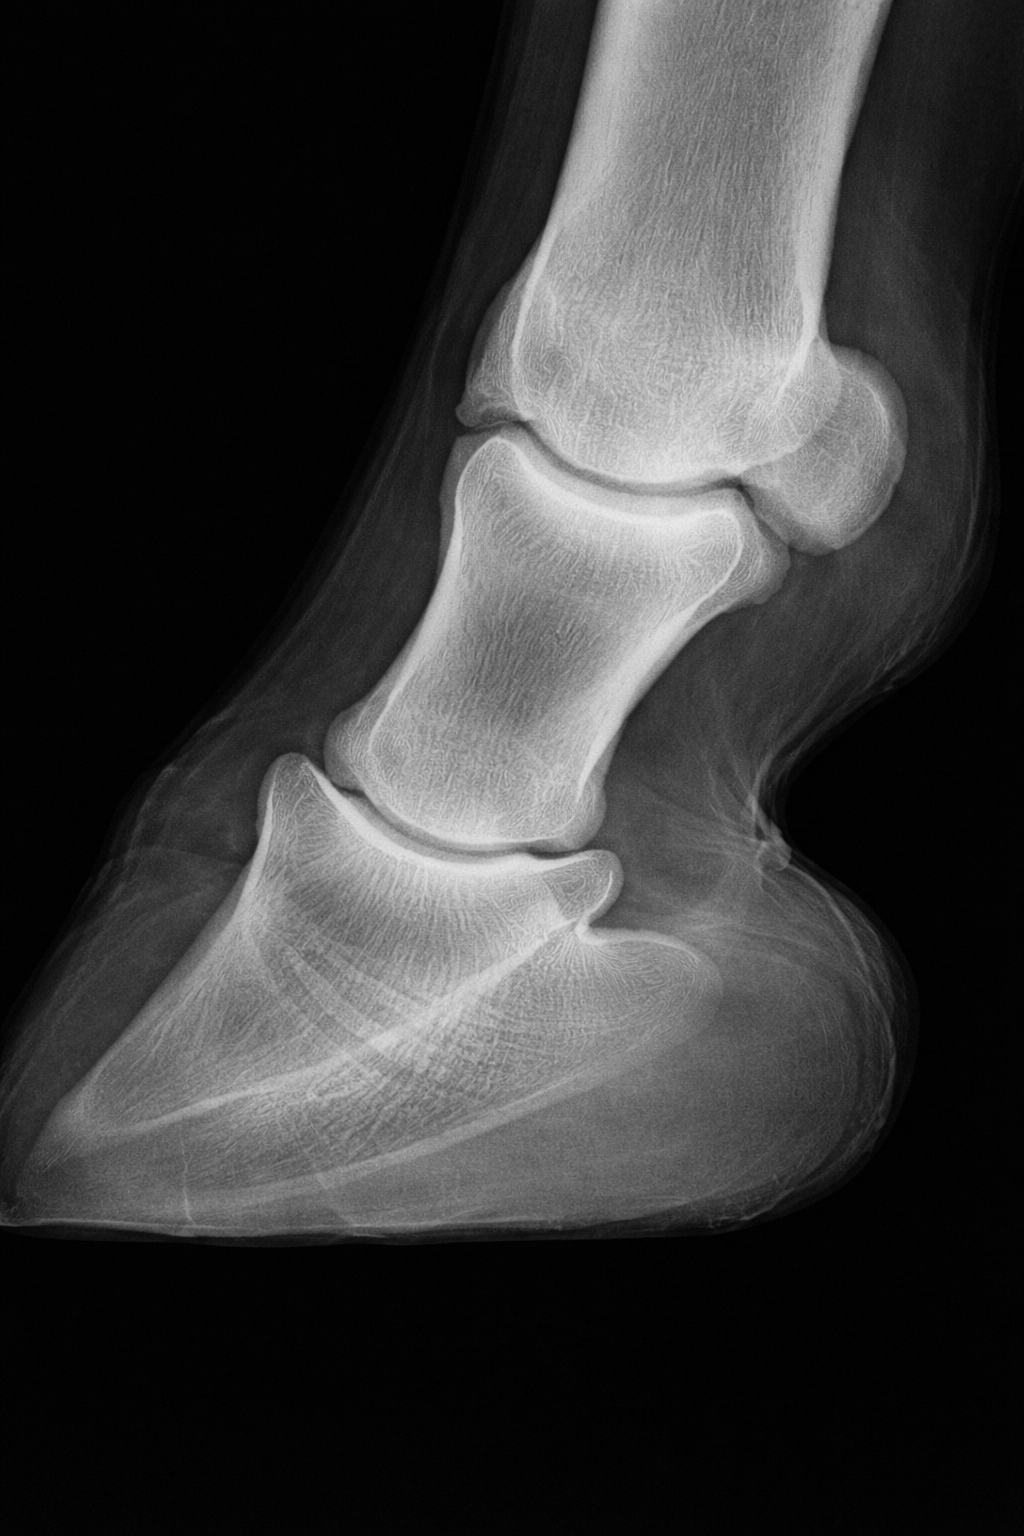

The viewing room was small and cramped. Light boxes on both walls. Four X-rays clipped up, glowing white against dark film.

Dr. Filkins pointed to the first one.

“This is the navicular bone,” he said. “It should look like a dowel. Smooth. Even.”

He moved to the next film.

“This is Tex’s.”

I’d seen plenty of X-rays during my years in small animal clinics. I knew what healthy bone looked like.

Tex’s navicular bones—both of them—looked like number-two pencils a nervous bookie had been chewing on. Pitted. Irregular. Damaged in a way that had clearly been building for a long time.

“Both front feet,” Dr. Filkins said. “This has been going on for a while.”